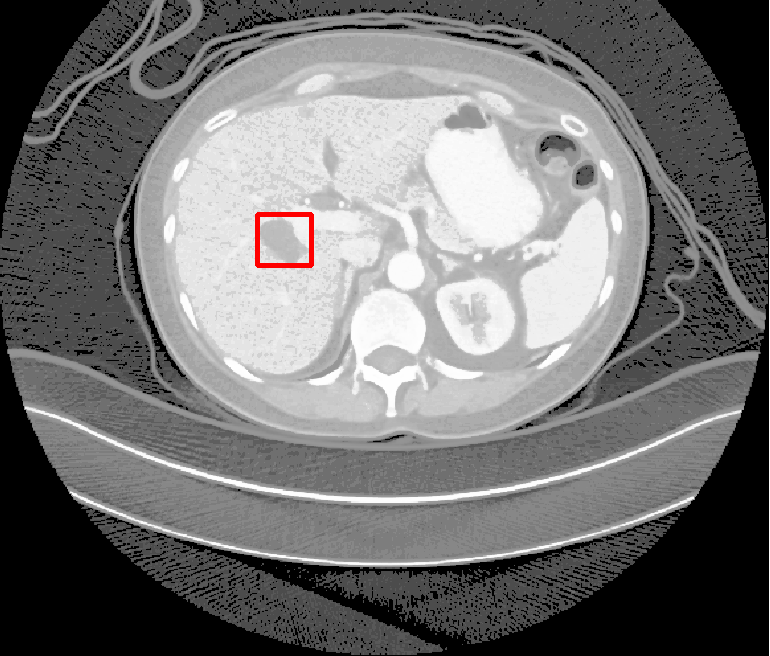

| (a) Ground Truth | (b) Faster R-CNN | (c) FPN | (d) Proposed |

In real-world scenarios, body lesions usually have arbitrary size. For instance, in the DeepLesion [14] dataset, the lesion size ranges from 0.21 mm to 342.5 mm. Since most of the established CNNs are not robust to handle such spatial scale variations, they have unpredictable behavior in the varying cases. As shown in Fig. 1, both Faster R-CNN and FPN fail to detect tiny lesions in the first row, while they produce small false positive lesions around the actual large lesion locations in the second and third rows.